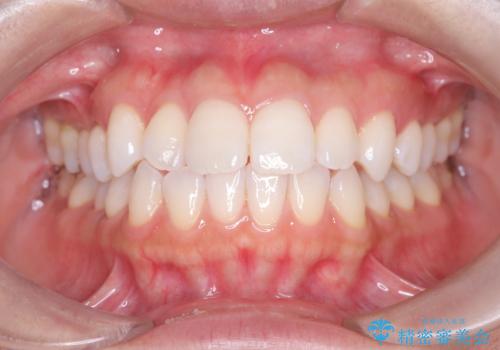

「歯を抜かずに、たった10ヵ月。」目立ちにくい大人の矯正

- 歯の捻じれやデコボコを主訴にご来院された患者様です。

矯正治療の精密検査を行った結果、非抜歯(歯を抜かない)矯正治療を選択いたしました。

その結果、約10ヵ月という比較的短期間で歯列と咬み合わせが整い、機能面・審美面ともに良好な結果を得ることができました。